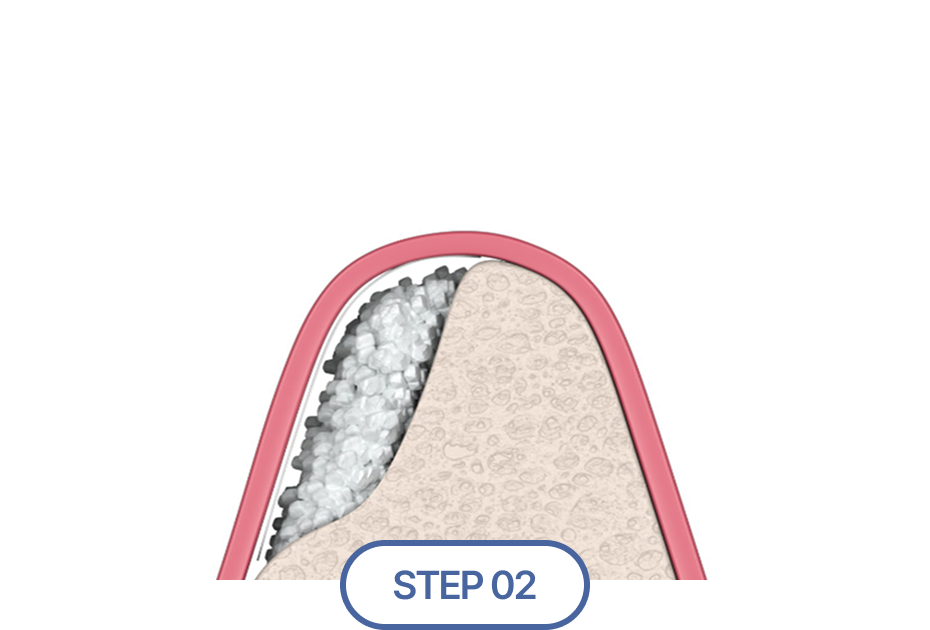

식립 할 위치에 인공뼈 이식

이 경우 뼈이식술을 통해 먼저 잇몸뼈의 양과 질을 개선한 후

임플란트를 식립 해야 장기적인 안정성과 성공률을 높일 수 있습니다.

임플란트에서 중요한 부분은 두꺼운 뼈와 건강한 잇몸에 있습니다.

뼈가 안 좋아 임플란트가 어려울 경우, 임플란트 식립을 위해

약해진 잇몸뼈를 이식하여 임플란트의 장기적인 수명을 향상시킵니다.